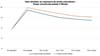

O volume médio de gordura enxertada foi de 116,7 mL no grupo de enxerto decantado e 123,3 mL no grupo de enxerto filtrado. A espessura média inicial do tecido subcutâneo era de aproximadamente 11 mm em ambos os grupos, aumentando para 22 mm no pós-operatório imediato no grupo decantado e 23 mm no grupo filtrado.

Houve reabsorção progressiva em ambos os grupos. A evolução da espessura subcutânea média em ambos os grupos está descrita na ►Tabela 1 e na ►Fig. 5.

| Período operatório | Grupo enxerto decantado (n = 6) | Grupo enxerto filtrado (n = 6) |

|---|---|---|

| Pré-operatório | 11,27 | 11,23 |

| Pós-operatório imediato | 22,42 | 23,90 |

| 15 dias de pós-operatório | 20,20 | 22,05 |

| 1 mês de pós-operatório | 18,10 | 20,35 |

| 3 meses de pós-operatório | 17,13 | 18,96 |

| 6 meses de pós-operatório | 16,51 | 18,46 |

No grupo enxerto decantado, a reducãomédia, comparando-se a espessura inicial apos lipoenxertia, foi de 9,90% no 15° dia, 19,27% no 1° mes, 23,59% no 3° mes e 26,36% no 6° mes. No grupo enxerto filtrado, a reducao media, comparando-se a espessura inicial apos lipoenxertia, foi de 7,74% no 15° dia, 14,85% no 1° mes, 20,67% no 3° mes e 22,80% no 6° mes. ►Fig. 6. A evolução ao ultrassom da espessura do tecido subcutâneo antes e depois da lipoenxertia pode ser vista nas ►Figs. 7-8. Os resultados de pré-e pós-operatório de uma paciente de cada um dos grupos estão exibidos nas ►Figs. 9-10.

A comparacao da reducao da espessura subcutanea em 6 meses entre as te cnicas de decantai; a o e filtrai; a o do enxerto na o mostrou diferenc a estatística significativa (p = 0,59).